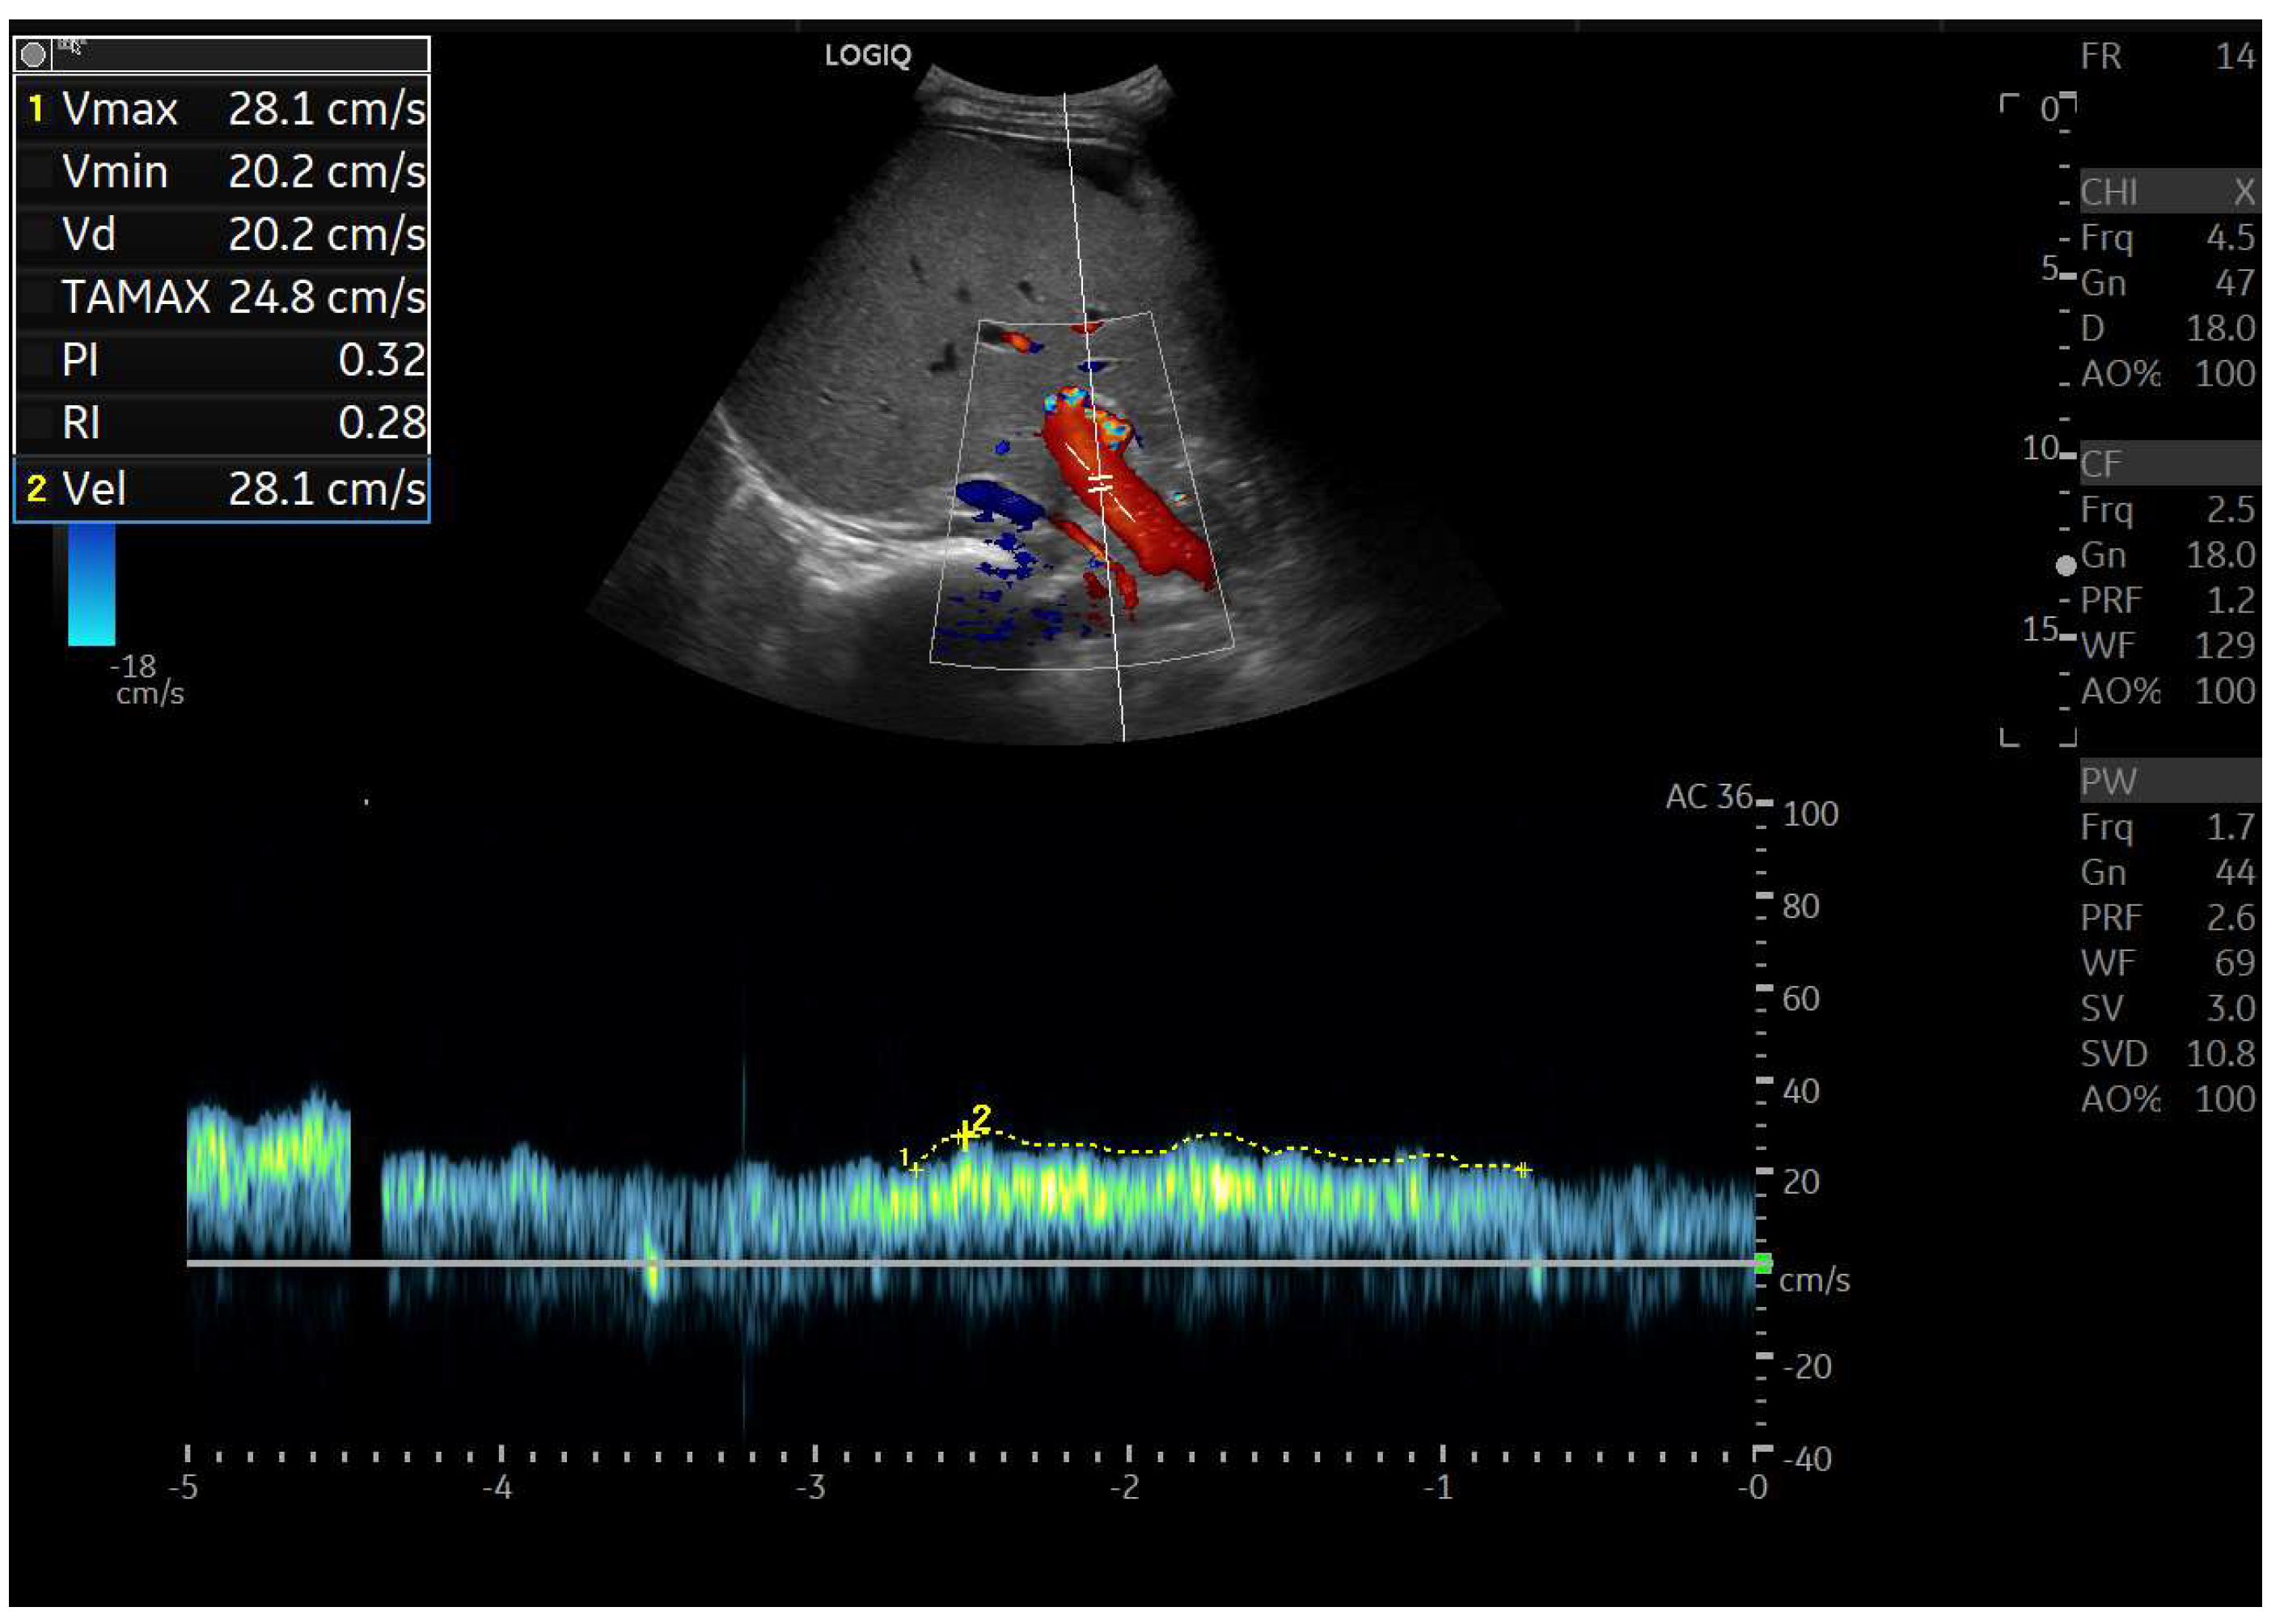

Doppler patterns in Fontan patients resemble those observed in chronic liver disease, including reduced portal flow velocity (mean flow velocity < 14 cm/s) [56]. The Fontan procedure inevitably alters hepatic venous waveforms on Doppler US (Figure 10, Figure 11, Figure 12 and Figure 13). Inverted portal flow has a specificity of 100% for diagnosing PHTN [57] (Figure 12). The hepatopetal phase pattern in the hepatic vein differs between patients with total cavo-pulmonary anastomosis (including both lateral tunnels and extracardiac conduits) and those with atrio–pulmonary connection [58,59,60]. In atrio–pulmonary connection, hepatopetal flow is preserved (Figure 10), reflecting the exclusion of atrial contribution to venous circulation, whereas in total cavo-pulmonary anastomosis, flow reversal (Figure 11) occurs only during early expiration. Similarly to congestive heart failure, hepatic veins and the IVC are dilated, with abnormally increased hepatic vein pulsatility, regardless of the anastomosis technique [54,61,62]. The loss of the normal three-phase Doppler pattern in hepatic veins is universal following bi-cavo-pulmonary surgery due to the absence of atrial contraction. The presence of a monophasic pattern indicates advanced liver injury [63].

Among individuals with Fontan physiology, the hepatic veins typically show a dampened, predominantly hepatopetal monophasic waveform, reflecting the presence of long-standing hepatic congestion. Venous flow velocities are markedly reduced compared with those measured in healthy individuals [63,64]. In contrast, in later stages characterized by cirrhosis and increased hepatic stiffness, further dampening or paradoxical changes in the venous flow pattern may be observed [37,56,64].

In particular, the hepatic venous Doppler waveform offers valuable insight into hemodynamic changes over time. In the early post-Fontan period, in the absence of atrial contraction and before structural liver damage is evident, the hepatic venous flow may display a relatively blunted monophasic or biphasic waveform with reduced phasicity, reflecting the lack of pulsatility and elevated central venous pressure [37,56,64].

As FALD progresses, and especially in the setting of developing cirrhosis, the Doppler waveform may become more dampened or even flat, corresponding to the increasing stiffness of the hepatic parenchyma, reduced compliance of the vascular bed, and worsening portal hypertension [37,56,64]. Simultaneously, the hepatic veins may appear dilated in the early and mid-stages of disease due to chronic venous congestion, but may show reduced caliber in later stages as fibrosis progresses and vascular remodeling occurs [37,56,64].

Tracking these Doppler changes, from waveform morphology to vein diameter, could provide a non-invasive, dynamic marker of FALD evolution. Including representative Doppler images at different timepoints post-Fontan would help clinicians recognize these transitions and potentially stratify risk or guide surveillance intensity.

Interestingly, hepatic vein waveform analysis can also serve as a surrogate marker for cardiac index, providing indirect insight into the hemodynamic status of Fontan circulation. Post-Fontan, IVC and hepatic vein dilation is common, but the main and intrahepatic portal veins tend to be small, likely due to reduced portal perfusion secondary to increased sinusoidal pressure and venous stasis [65]. The lumen width depends on the severity of the liver cirrhosis and, presumably, the duration of the disease. In FALD, the chronic elevation of central venous pressure leads to venous congestion and dilation of the hepatic veins and IVC due to the following reasons: the Fontan circulation results in chronically elevated systemic venous pressure, which is transmitted directly to the hepatic veins via the IVC [37,56,64]. Over time, this causes passive venous dilatation, which can persist or even worsen despite progression to fibrosis and cirrhosis. Thus, even in advanced congestive cirrhosis from FALD, the hepatic veins and IVC often remain dilated [37,56,64]. This is in contrast to classic cirrhosis from other etiologies, where fibrotic contraction can narrow venous structures.

A controlled study of 106 individuals by Kutty et al. found higher resistance and pulsatility indices in the celiac trunk and mesenteric artery, along with a significant decrease in portal velocity in Fontan patients [64]. These changes can be observed in cirrhosis of any etiology as they reflect hemodynamic consequences of cirrhosis in general. In advanced cirrhosis, increased intrahepatic vascular resistance leads to reduced portal inflow, which causes a compensatory increase in arterial inflow. Over time, changes in downstream compliance and resistance cause elevated RI and PI in splanchnic arteries. In FALD, the portal flow is often lower than in other cirrhosis types, and hepatic artery compensation may be more marked. Tellez et al. [66,67] describe that the portal hypertension model in FALD is characteristically hypodynamic and arterial splanchnic perfusion may also be impaired, as shown in Doppler studies. Indeed, this is what makes FALD a unique entity.